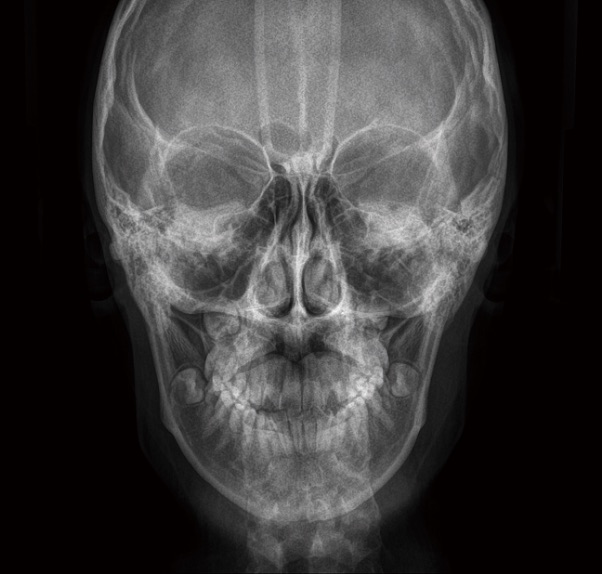

セファロAP方向撮影